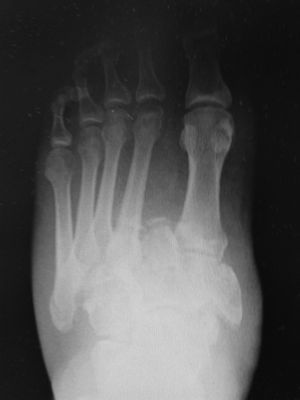

Una vez finalizado el tratamiento, y ante la escasa respuesta al mismo dado que no se apreció mejoría del cuadro doloroso ni inflamatorio, se decide realizar una radiografía anteroposterior, lateral y oblicua de pie donde se objetiva fractura-luxación tipo Lisfranc con afectación a varios niveles de la articulación tarso y metatarsal (fig. 2). Ante estos hallazgos, el paciente fue derivado a urgencias de traumatología de su hospital de referencia para valoración descartándose intervención quirúrgica urgente. Se inició estudio ambulatorio de afectación mediante tomografía axial computarizada para valoración del daño ligamentoso y valoración de forma diferida en consultas externas de traumatología.

El diagnóstico es de sospecha en primera instancia ante cualquier paciente diabético mal controlado de larga evolución que se presenta en la consulta con signos inflamatorios y edema unilateral del pie, de inicio insidioso, con leve dolor e incluso ausencia del mismo4. Para conocer la afectación, se realiza radiografía anteroposterior, lateral y oblicua objetivándose un aumento de la diástasis (usualmente >2mm). Esta técnica no suele ser suficiente para poder saber el grado de afectación, por lo que para el estudio de estructuras adyacentes como tejidos blandos y ligamentos se realizan resonancias magnéticas y tomografías axiales computarizadas, que aportan gran información para el acto quirúrgico y elegir el mejor tipo de intervención5.